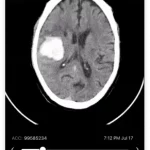

- Identifies eligible patients faster with AI-powered disease detection

- Real-time access to hospital imaging

- Identifies clinical trial patients at the time of evaluation